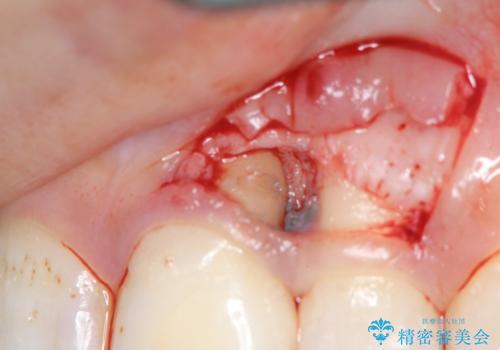

X線検査を行い診断的な小手術を行ったところ、歯に亀裂があり修復が不可能な状態であることがわかりました。

長期的な予後を見通すことが難しかったので、亀裂のある前歯の抜去を行いブリッジで審美性・機能性の回復を行いました。